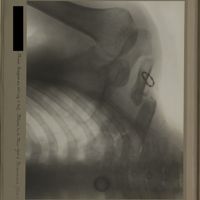

0151 - Page 39 - [Radiographie de la hanche]0151 - Page 39 - [Radiographie de la hanche]

0190 - Page 78 - [Radiographies de la hanche]0190 - Page 78 - [Radiographies de la hanche]

0196 - Page 84 - [Radiographie de la hanche]0196 - Page 84 - [Radiographie de la hanche]